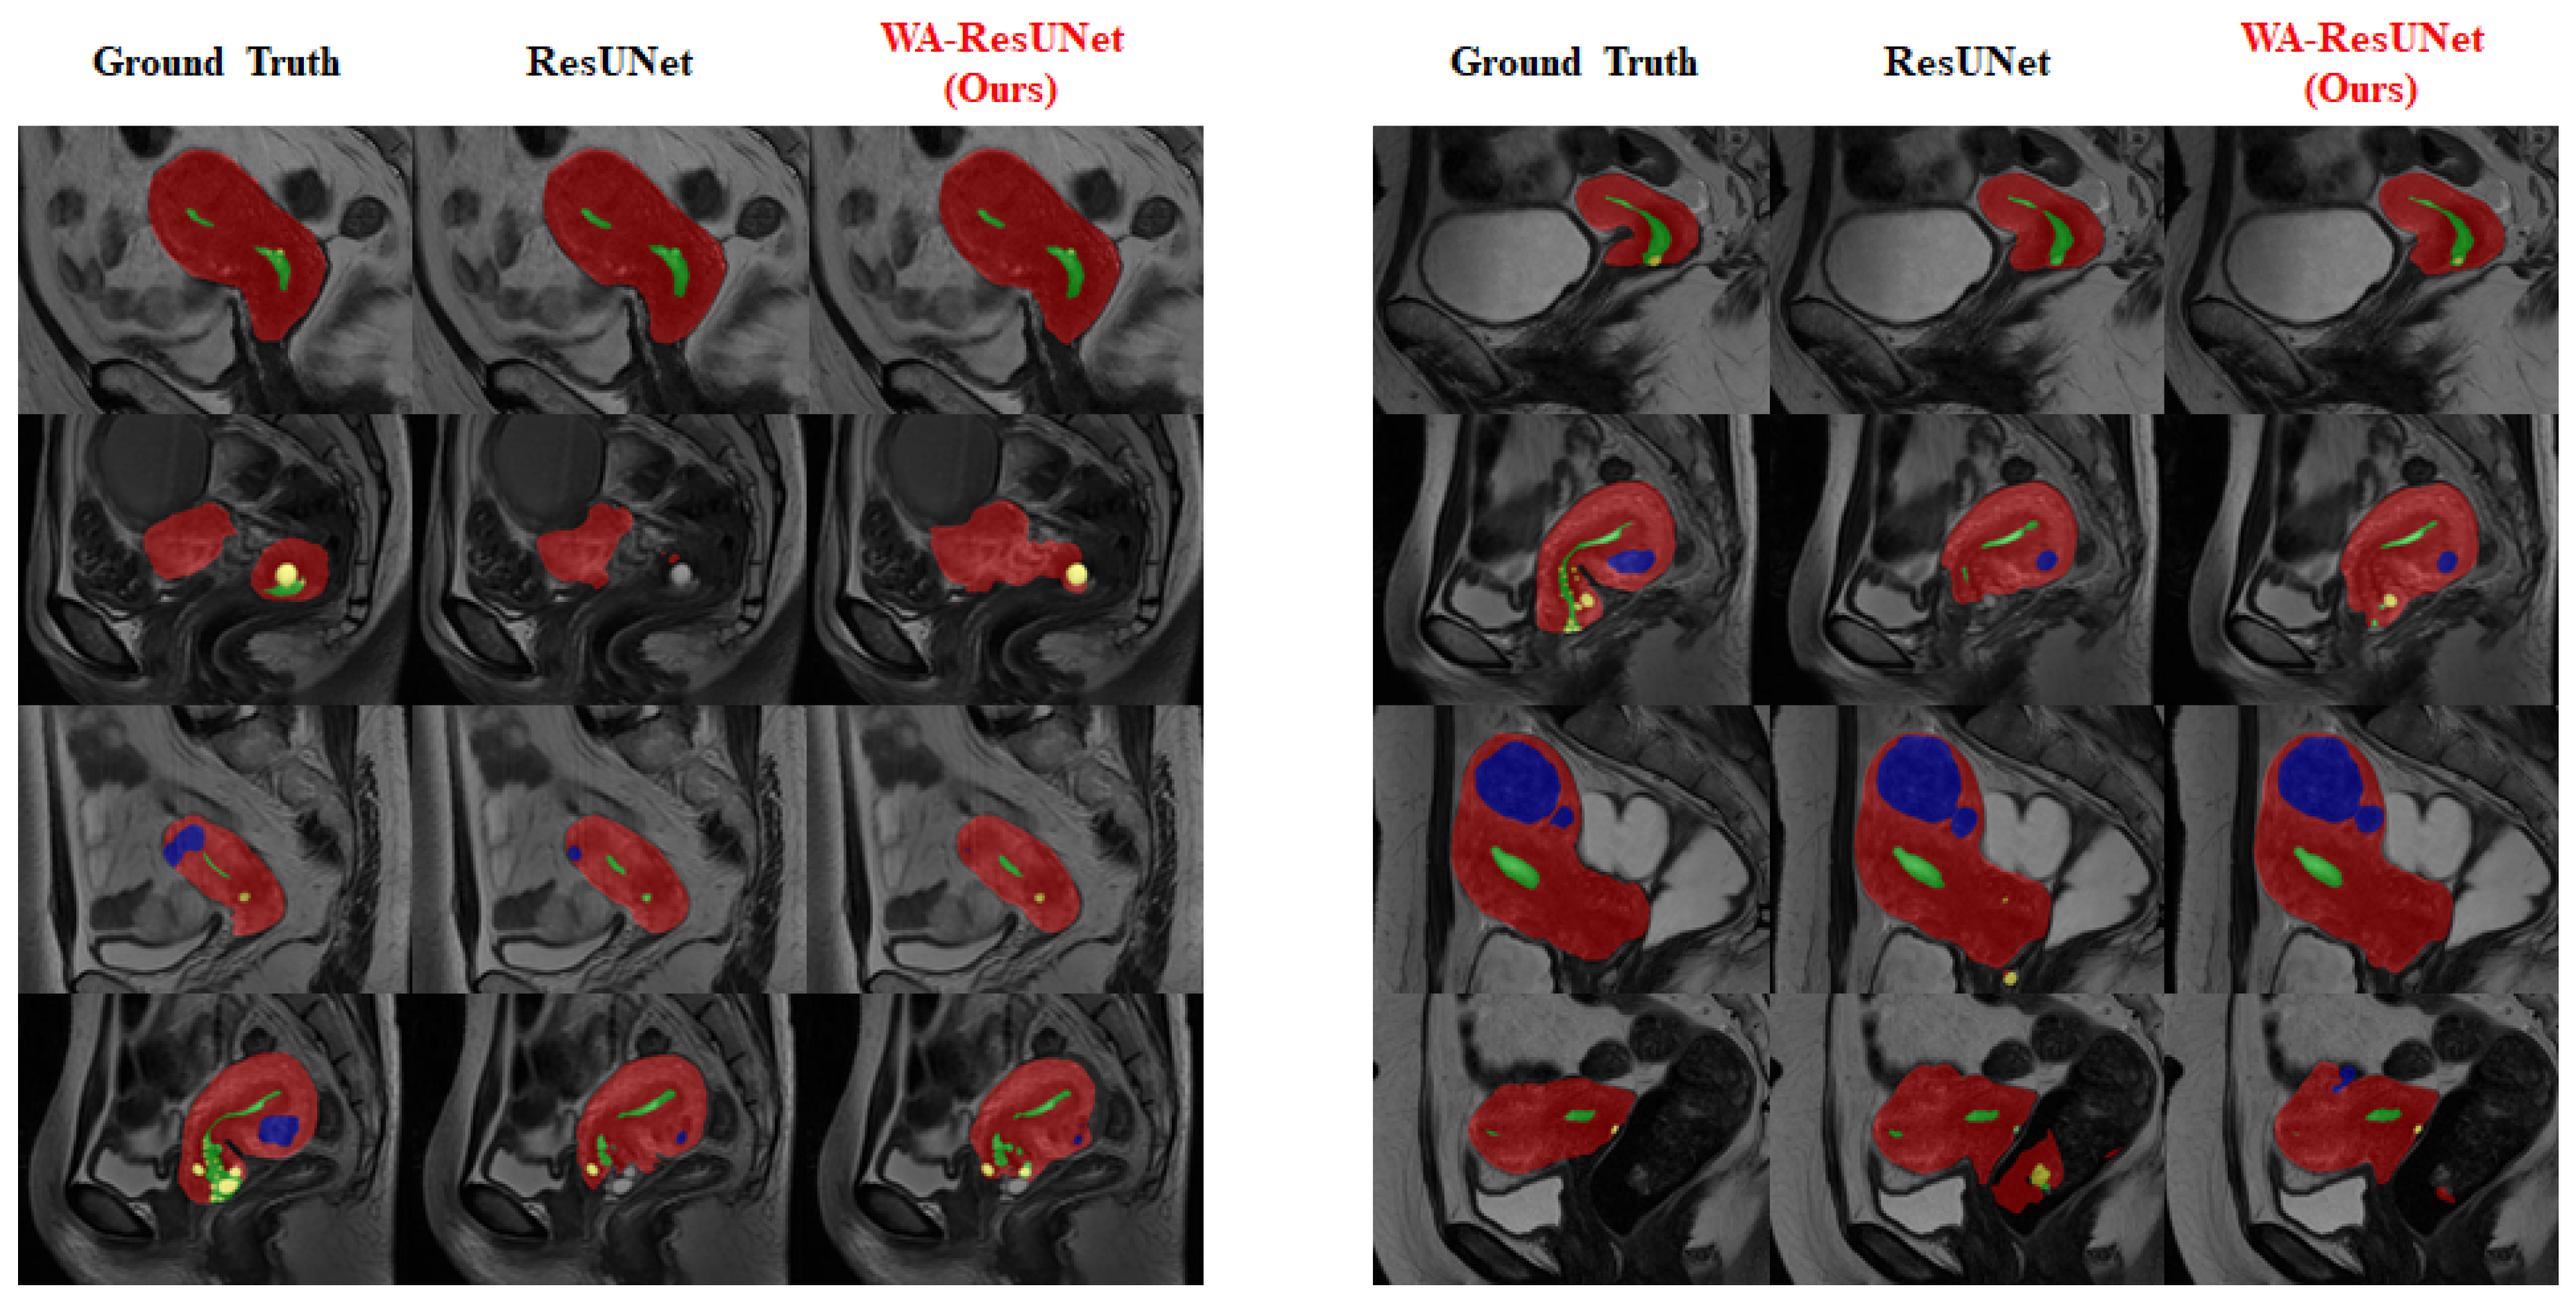

To provide a clearer visualization of the improvement in the segmentation effect of the low-frequency class achieved by our model, we conducted visualization processing on the experimental reasoning results. The visualized results are presented in Figure 7 and Figure 8.

Figure 7 mainly reflects the overall predicted situation and describes the difference between the precision and sensitivity ratio of the predicted results, and Figure 8 shows the improvement of the model in the low-frequency class (nabothian cyst).

Figure 7. Comparison of visual inference results—overall: The three columns of the images show the predicted values of the expected baseline and the predicted values of our proposed model, respectively. During visualization, the uterine wall was covered in red, the uterine cavity was covered in green, myomas of the uterus were covered in blue, and nabothian cysts were covered in yellow.